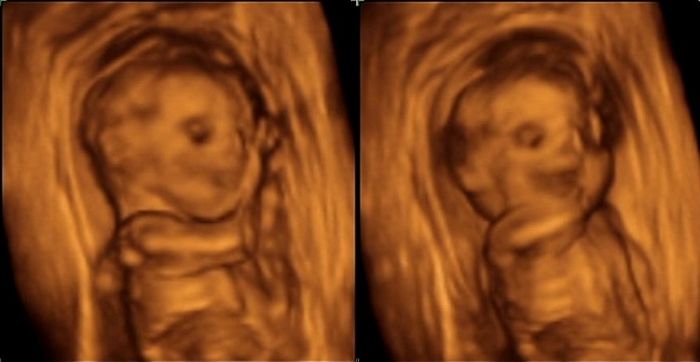

Ahoj holky,tak máme 3D UZ za sebou,ale teda čekala jsem od toho asi víc,po tom co sem tu viděla i opravdu nádherné a detailní fotky..

Doufala jsem,že ta tvářička bude vidět líp,ale to prý bývá nejhezčí až tak kolem 28tt..

Taky teda ještě asistentka říkala,že když je placenta na přední straně,je tam ta viditelnost prý mnohem horší,než když je uložená vzadu za miminkem a u nás to k tomu ještě komplikoval fakt,že ty placenty mám dvě,přesně naproti sobě a mrňous byl mezi ně dost natěsno..

Takže asi tak no...Nemůžu říct,že to nebyl hezký zážitek a vzpomínka,aleza ty peníze sem asi čekala trošku lepší výsledek..

POsílám pár 3D fotek + 2D fotku dvou placent..

Adri,na te jedne vypadá opravdu jako by se smál..

ALe pak na te další zase má opravdu vzpurný výraz..

Nakonec prý bylo asi lepší že jsme šli teď,jelikož za 2 týdny by přes ty placenty mohlo být vidět uplny kulový,prootže je na UZ dost dobře vidět,jak obě poměrně rychle s mimčem rostou..